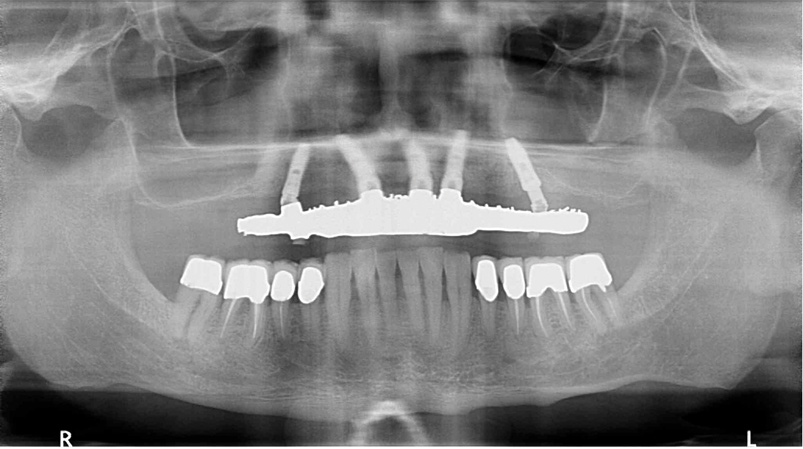

Fig 12. Preoperative radiograph revealed the location and spacing of previously placed implants.

Figure 12

A 74-year-old woman was referred for treatment of extensive and unesthetic wear of her mandibular teeth (Figure 11 and Figure 12). Her left posterior tooth and right posterior and premolar teeth were implants; three different implant systems had been previously placed by the same dentist on the same day. Her maxillary teeth had been previously restored with zirconia full-coverage restorations.